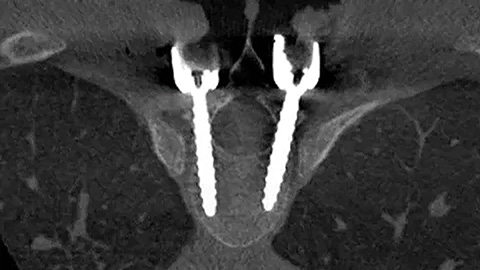

Provides better insights into spinal anatomy to support precise planning and guide effective implant placement.

The Azurion system is the optimal balance between intraoperative image quality and radiation exposure for surgeons and patients."

Spine suite results one pager Key benefits of Azurion with FlexMove for spine surgery